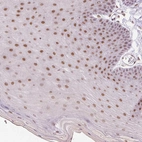

Immunohistochemical staining of human skin shows moderate nuclear positivity in squamous epithelial cells.